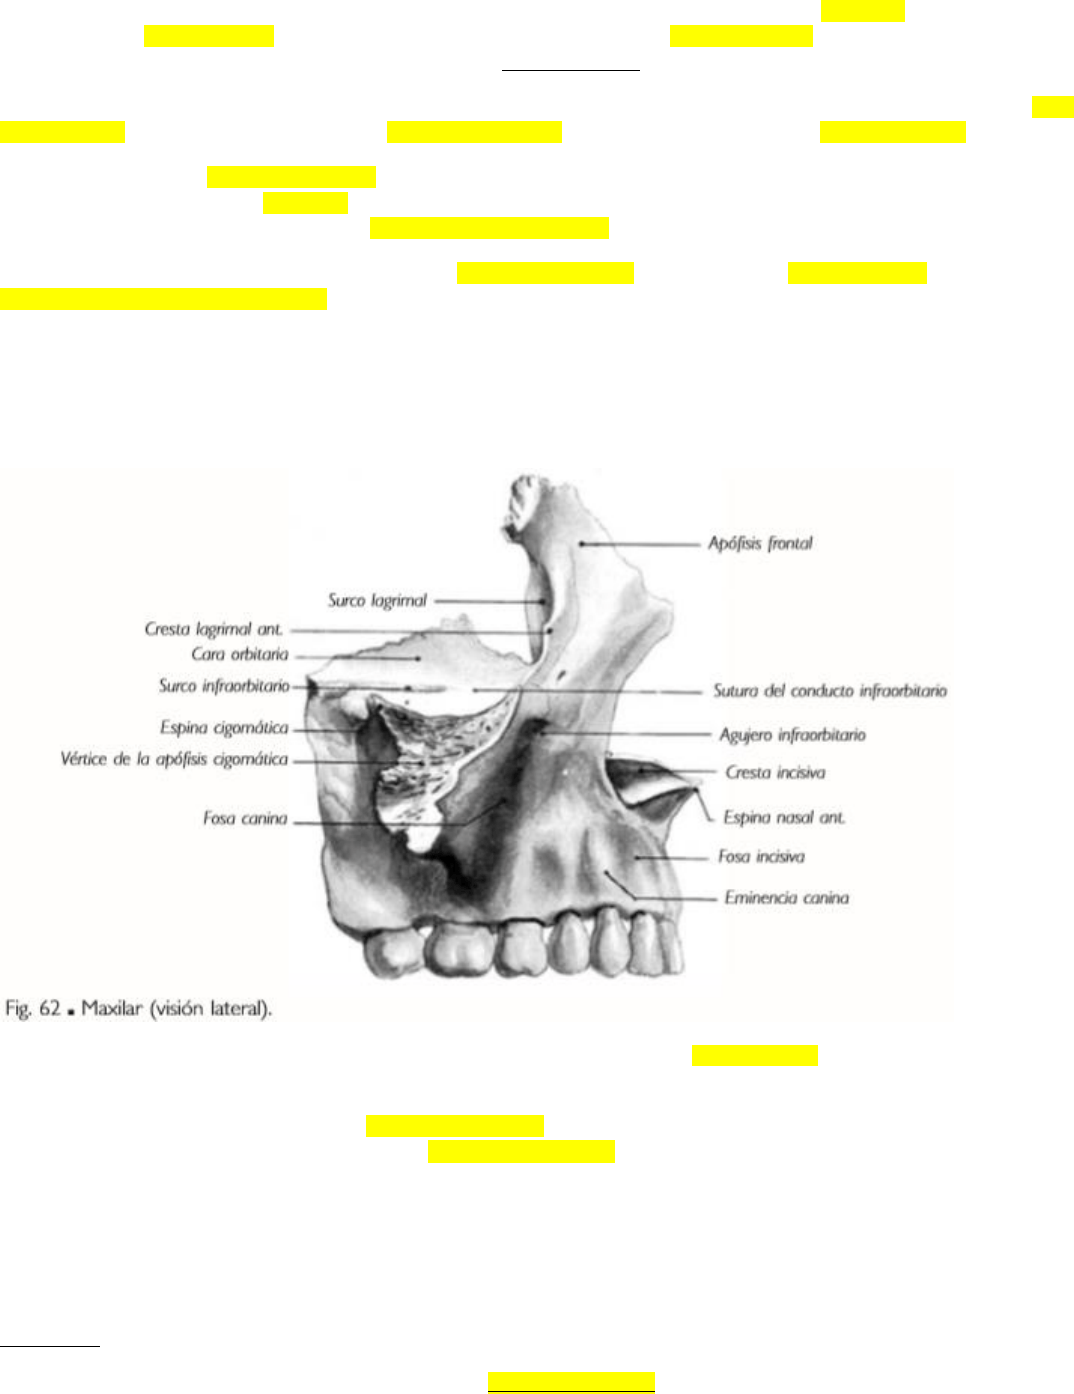

B. VISTA LATERAL: en su parte anterior, encima de la implantación de los incisivos, se observa una depresión: la fosa canina, limitada por detrás

por una saliente, la eminencia canina. Por detrás y encima de esta eminencia, se destaca la apófisis cigomática, que se une por su base al resto del

hueso; su vértice truncado se articula con el hueso cigomático. En la apófisis cigomática se describen:

- Cara orbitaria [superior]: plana, forma parte de la pared inferior de la cavidad orbitaria; está separada del ala mayor del esfenoides por la fisura

orbitaria inferior. Un canal aloja al nervio maxilar: el conducto infraorbitario, que continúa en esta pared como surco infraorbitario.

- Cara anterior: presenta el foramen infraorbitario, terminación del conducto precedente, por donde emerge el nervio infraorbitario. Debajo de

este foramen hay una depresión: la fosa canina. De la parte inferior del conducto infraorbitario, en el espesor del hueso, se originan conductos que

terminan en los alvéolos del canino e incisivos: los canalículos dentarios anteriores.

- Cara infratemporal: convexa, corresponde medialmente a la tuberosidad del maxilar, y lateralmente, a la fosa infratemporal. Presenta

forámenes alveolares [dentarios posteriores] destinados a los nervios del mismo nombre y a las arterias alveolares para los molares.

- Borde inferior: cóncavo hacia abajo, es grueso y convexo en sentido anteroposterior.

- Borde anterior: forma la parte media e inferior del borde orbitario.

- Borde posterior: contribuye a delimitar la fisura orbitaria inferior.